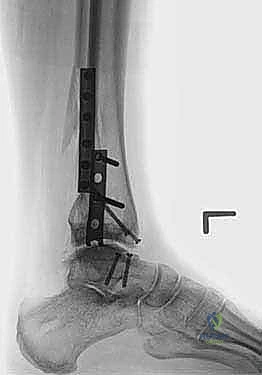

صور إضافية من داخل غرفة العمليات والخطوات الجراحية

ندرك أهمية توثيق الخطوات الجراحية لطلاب الطب والمرضى الراغبين في فهم دقة الإجراء. هذه الصور توضح مراحل زراعة وتثبيت الطعم العظمي الغضروفي بدقة متناهية تحت إشراف أ.د. محمد هطيف.